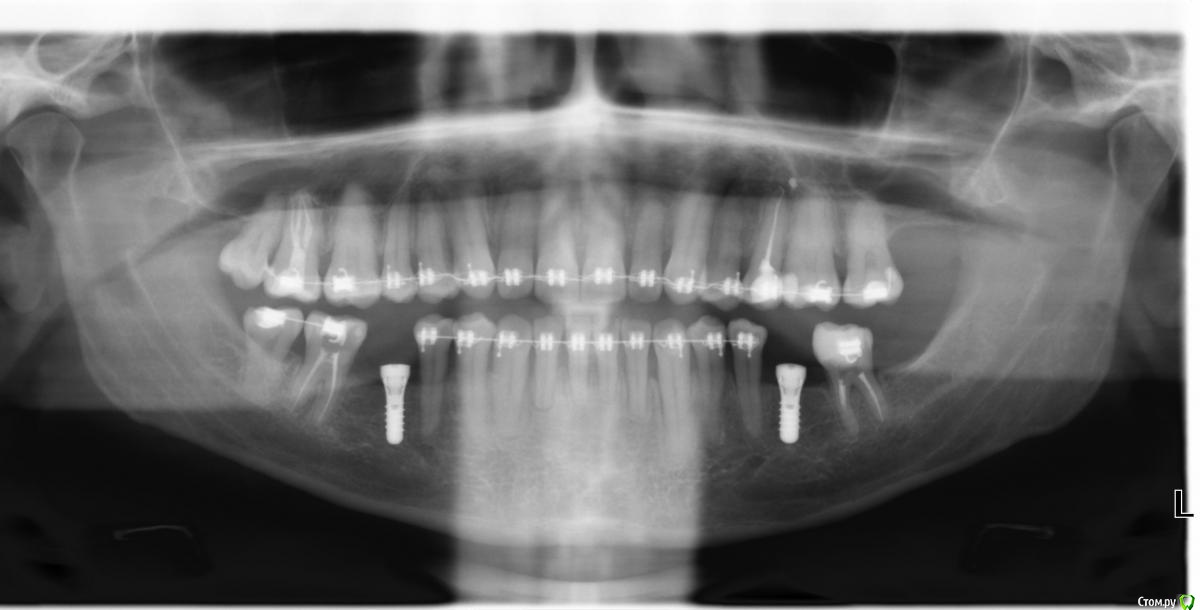

Михаил Н. Опубликовано 23 августа, 2018 Поделиться Опубликовано 23 августа, 2018 Всем доброго здравия! Меня зовут Михаил, и у меня к вам, по-видимому, достаточно мудрёный вопрос) 14 июня я сделал имплантацию, двумя имплантами Straumann в область нижней челюсти.И где-то через две недели у меня начались странные ощущения в области шеи и глотки.Словно посторонний предмет застрял на уровне кадыка, плюс боль.В глотке ощущения, что жжет и болит. Воспалилось верхнее нёбо и задняя часть языка и тоже жжет и болит.Из-за этого пришлось 3 июля снять брекет-систему, хотя лечение и не было завершено. Спустя пару недель добавился сухой кашель, а недавно стало временами закладывать нос.Без выделений. И появилось новое ощущение - быстрая утомляемость при жевании. Уже побывал в больнице, где проверили, что это не щитовидка, не сердце, не лор-патология,и не бытовая аллергия. Аллергологи заявляют, что точный тест на титан и цирконий ничего не даст, слишком много сложностей. Мой стоматолог говорит, что импланты в порядке, не отторгаются. Нижнечелюстной нервне повреждён. СОИ не повышен - то есть воспаления нет. Однако получается, что симптомы потихоньку нарастают.Неврологи говорят - тревожное состояние и выписывают успокоительные. Которые не влияют ни на что)Был у фониатра - она сказала, что воспаление действительно есть, но отчего - не знает. Возможно и зубы. Может ли это быть тот самый случай индивидуальной непереносимости имплантов, или металлов в их составе?Или вялотекущей аллергии, или какой-нибудь гальваники.Это вроде бы материал Roxolid, то есть там Титан и Цирконий.И, если так, то выход у меня, насколько понимаю только один - удаление? Снимок (еще с брекетами) добавил Ссылка на комментарий